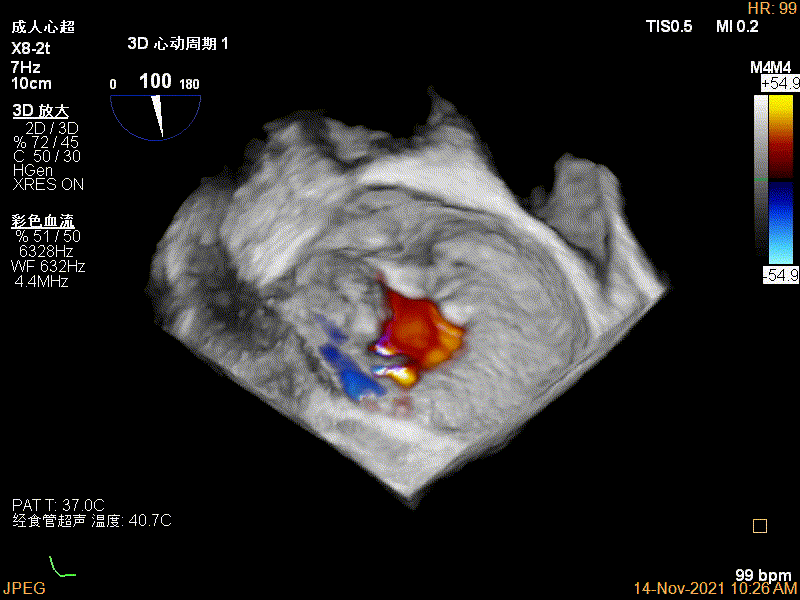

3D-color MV view:源自于交界区的大量反流

Qlab软件勾画估测瓣口面积约:6.52cm²

3Dcolor证实残余分流主要来源于残余脱垂

3D-color视图下两个夹子间少量残余反流